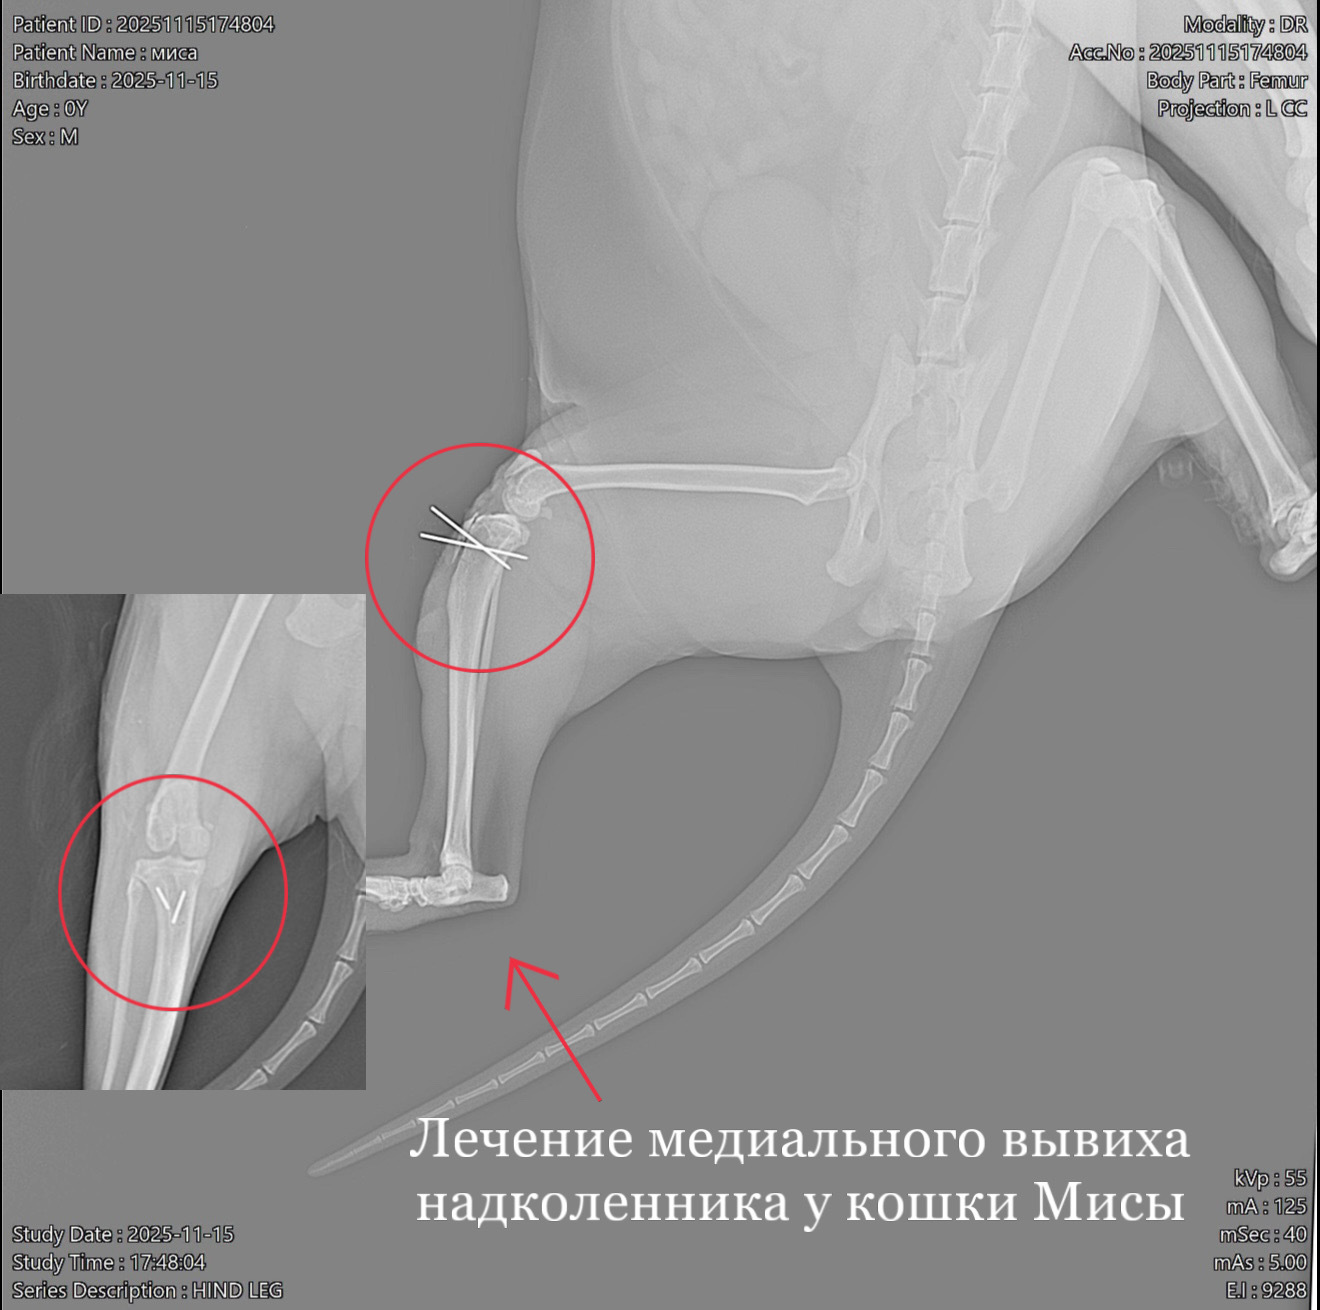

Ветеринарная травматология охватывает широкий спектр состояний: от вывихов и растяжений до сложных переломов. Ветеринар-травматолог применяет как консервативные методы (иммобилизация, медикаменты, физиотерапия), так и хирургическое вмешательство.

При сложных повреждениях используются остеосинтез, артроскопия и другие современные техники. Лечение проходит под контролем врача-анестезиолога, с учётом возраста и состояния животного.